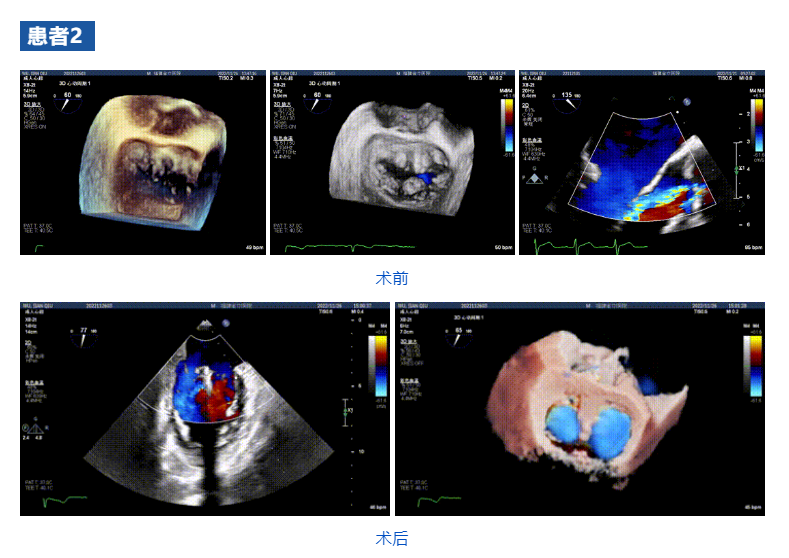

接受治療的三例患者均為器質性重度二尖瓣反流(DMR)患者,術前超聲提示二尖瓣后葉脫垂伴4+反流,左室舒張功能減退。郭延松教授攜同團隊成員陳新敬副教授和洪景宣、方明程、楊清勇主治醫師、心外科丁杭主任以及超聲科賴寶春、葉振盛主治醫師共同進行病情討論??紤]到患者高齡、基礎疾病多、STS評分高,為外科手術極高危患者,不適合進行外科開胸二尖瓣手術,因此決定為患者實施經導管緣對緣修復介入術(JensClip經導管瓣膜夾系統)。

在浙江大學醫學院附屬第二醫院王建安教授團隊的支持下,手術經股靜脈-房間隔入路,采用全身麻醉插管,在TEE和DSA引導下完成房間隔穿刺。置入JensClip瓣膜夾系統后,在左房調整瓣膜夾的位置和軸向,后進入左室,在TEE引導下捕捉二尖瓣前后瓣葉,并關閉瓣膜夾。經TEE反復確認手術效果后最終鎖定并釋放瓣膜夾。術后即刻超聲顯示瓣膜夾位置穩定,功能良好,二尖瓣反流由術前4+減少至微量,手術圓滿成功。